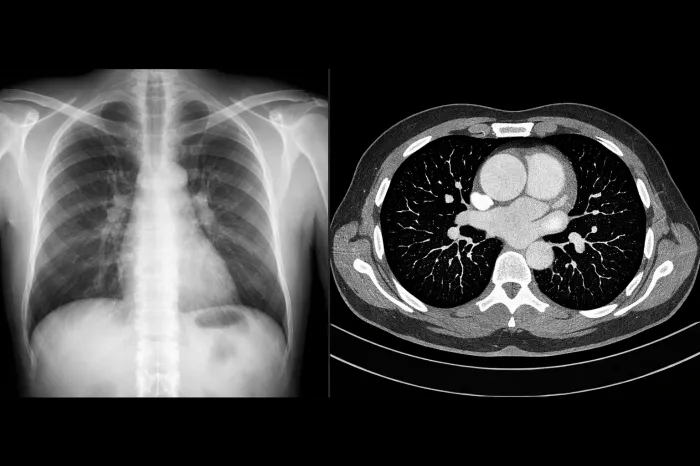

정기적인 영상 검사

폐결절이 발견되면 일정 간격으로 CT 검사를 통해 크기와 형태 변화를 확인합니다. 보통 3개월, 6개월, 1년 단위로 추적 관찰을 하게 되며, 변화가 없다면 검사 간격이 점점 늘어납니다.